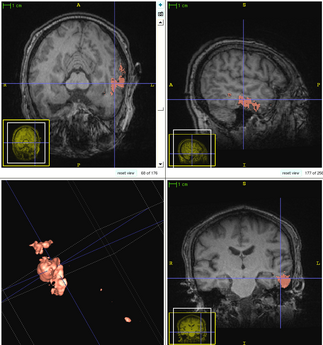

Patient-Specific Segmentation Framework for Longitudinal MR Images of Traumatic Brain Injury

We propose a multi-modal image segmentation framework for longitudinal TBI images [5]. The framework is initialized through manual input of primary lesion sites at each time point, which are then refined by a joint approach composed of Bayesian segmentation and construction of a personalized atlas. The personalized atlas construction estimates the average of the posteriors of the Bayesian segmentation at each time point and warps the average back to each time point to provide the updated priors for Bayesian segmentation. The difference between our approach and segmenting longitudinal images independently is that we use the information from all time points to improve the segmentations. Given a manual initialization, our framework automatically segments healthy structures (white matter, grey matter, cerebrospinal fluid) as well as different lesions such as hemorrhagic lesions and edema. Our framework can handle different sets of modalities at each time point, which provides flexibility in analyzing clinical scans.

Segmentation framework

The segmentation framework is initialized through manual input of primary lesion sites at each time point, which are then refined by a joint approach composed of Bayesian segmentation and construction of a personalized atlas. The following figure is the segmentation framework for multi-modal MR images.

The following two figures show the snapshot of the segmentation result.

Segmentation of acute images of subject I

Segmentation of chronic images of subject I